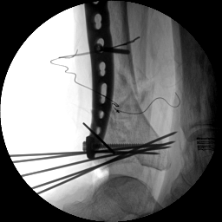

初步復(fù)位后X線

2.CO接骨機器人持續(xù)牽引維持復(fù)位,選擇前外側(cè)切口對前外側(cè)骨塊進(jìn)行撬撥復(fù)位,并用克氏針進(jìn)行臨時固定。C臂透視復(fù)位滿意,放置兩塊鋼板進(jìn)行固定。